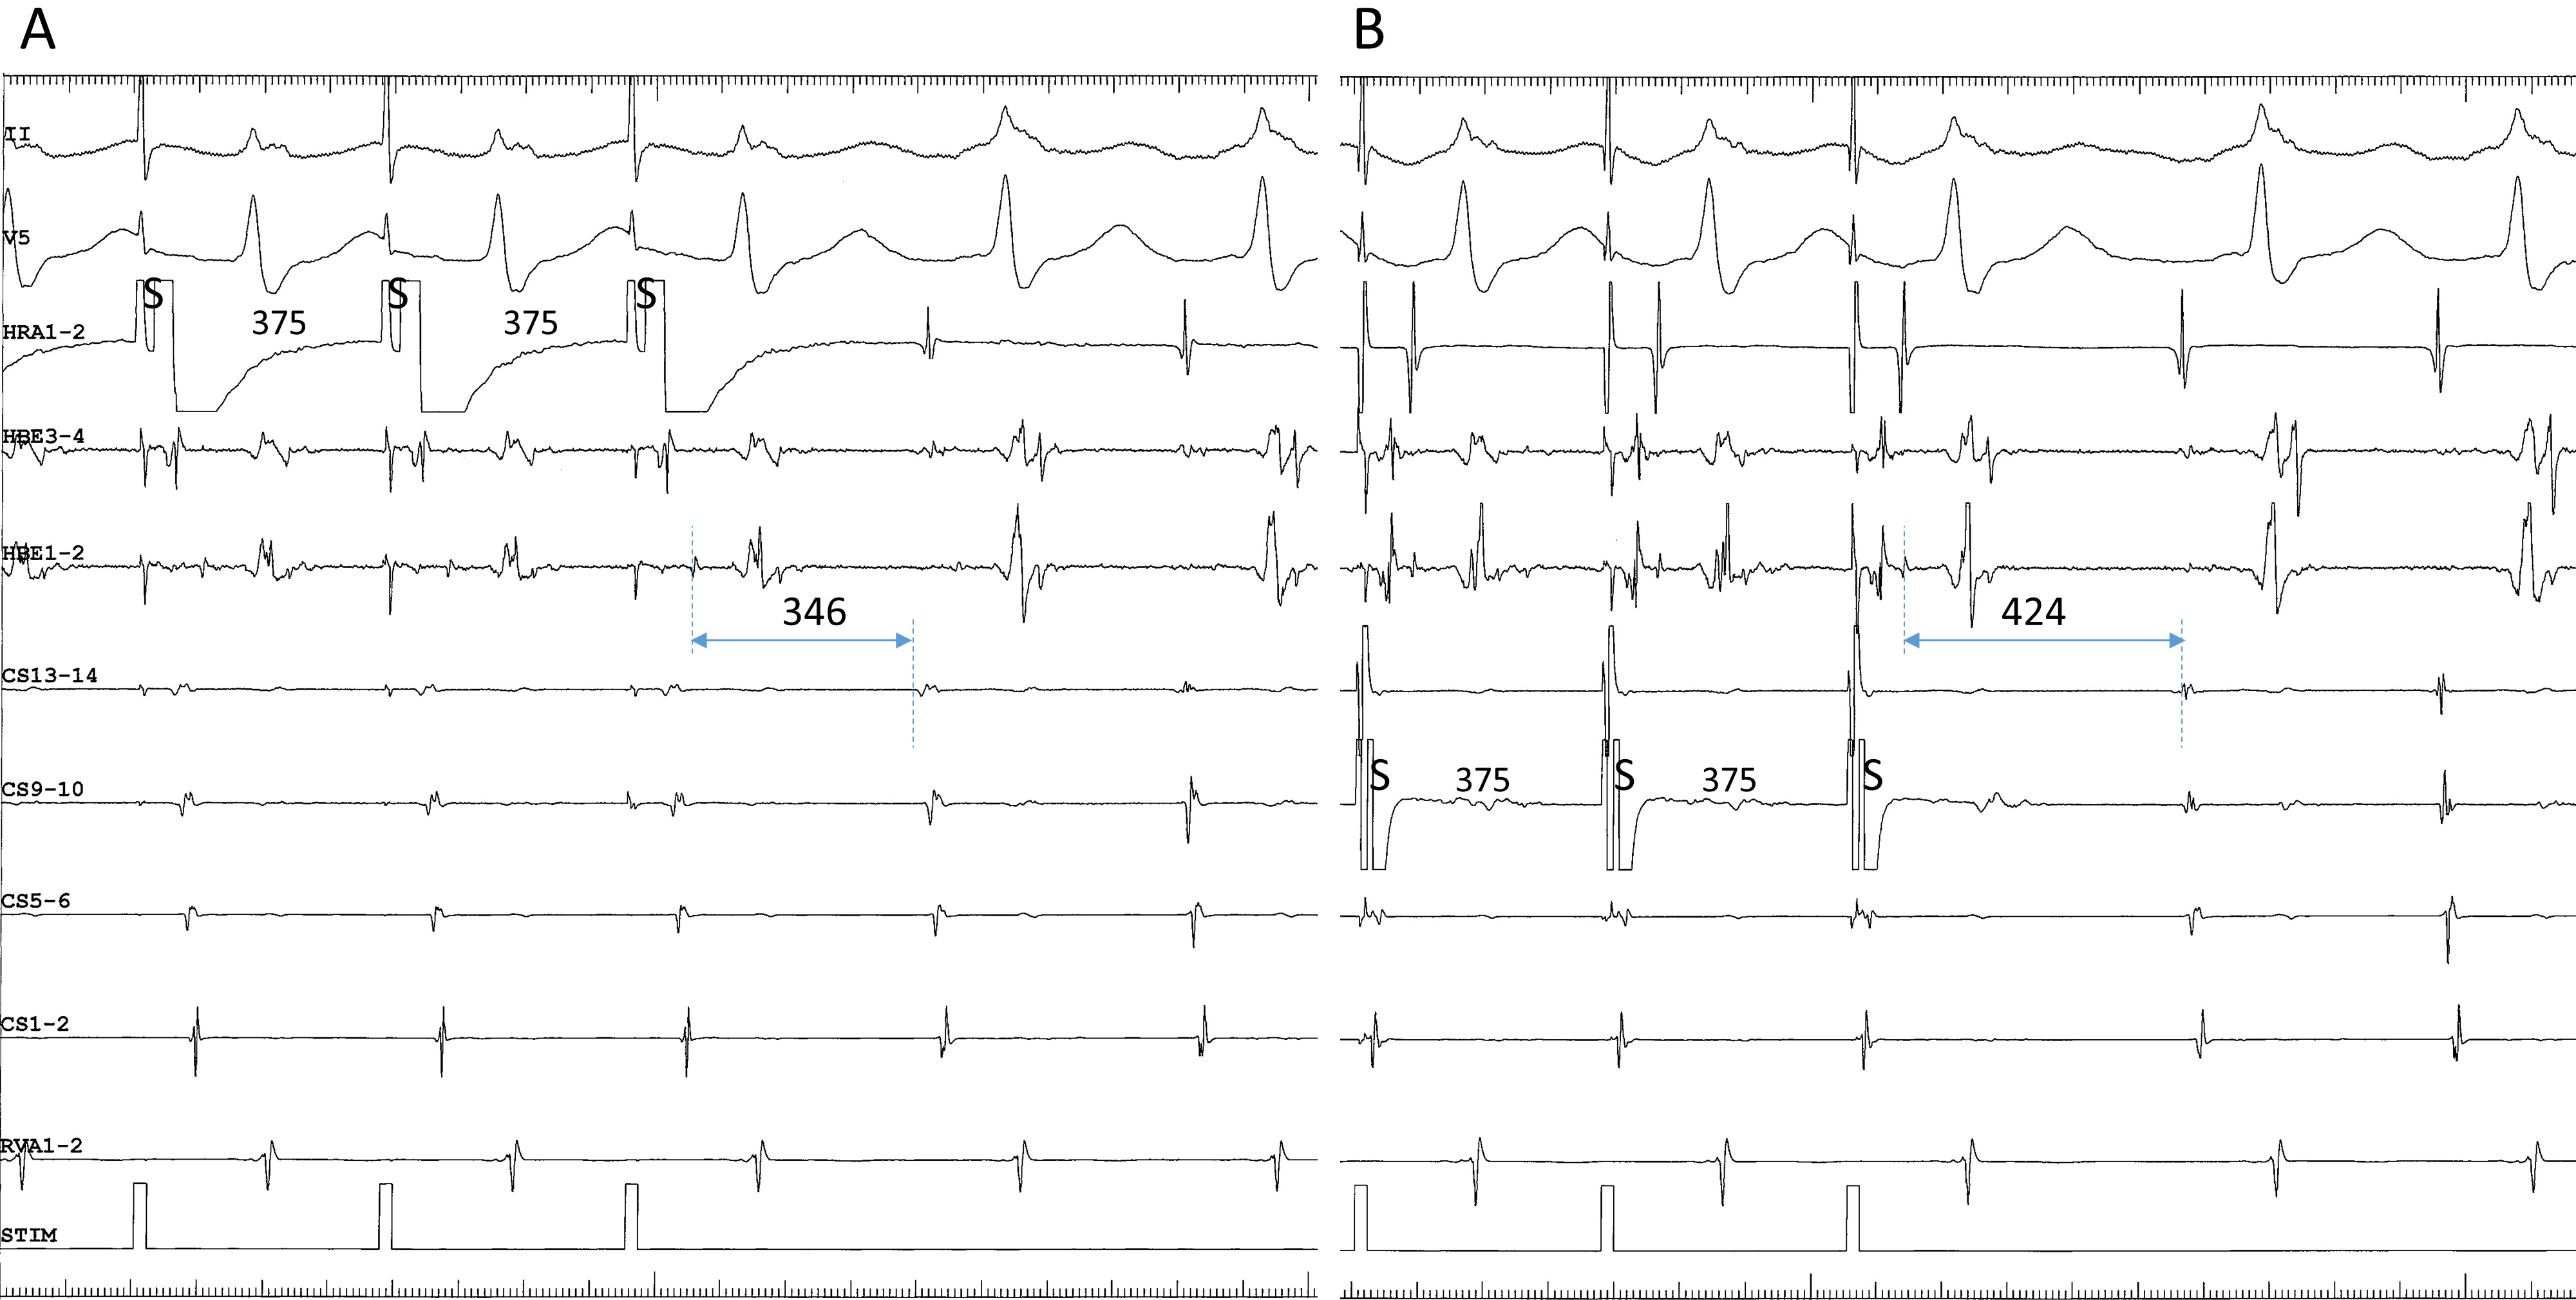

Fig. 5.Differential atrial entrainment pacing at an S-S cycle length of 365 ms from the high right atrium (HRA1-2) (A) and the proximal coronary sinus (CS9-10) (B), in a patient presenting with fast-slow AVNRT using an inferolateral, right atrial SP. This patient is the same as in Fig. 4D. Note: (1) the atypical atrial activation sequence during tachycardia, characterized by nearly simultaneous atrial electrograms in the HRA and in the His bundle region (HBE1-2); and (2) shorter His-atrial intervals immediately after entrainment pacing (indicated by horizontal bidirectional arrows and numbers above) in the HRA than in the proximal coronary sinus (CS9-10). II, surface electrocardiogram lead II; CS13-14 to 1-2, proximal to distal coronary sinus; RVA, right ventricular apex.

We present a unique response to differential atrial entrainment pacing of inferolateral fast-slow AVNRT. Differential atrial entrainment pacing of typical fast-slow AVNRT may reveal the absence of VA linking, characterized by a shorter VA interval after pacing from the proximal CS than from the HRA, due to the pacing site-dependent effect described earlier [35]. In contrast, differential atrial entrainment pacing of inferolateral, fast-slow AVNRT may reproducibly reveal a reverse relationship of the VA interval, characterized by a shorter VA interval after pacing from the HRA than from the proximal CS (Fig. 5). This may be due to the atypical location of the atrial end of the SP, relatively away from the proximal CS and closer to the HRA, causing a deeper penetration into the SP during pacing from the HRA than from the proximal CS. The subsequent retrograde conduction time over the SP is, therefore, shorter after pacing from the HRA than from the proximal CS. This information may be helpful when interpreting the results from differential atrial entrainment pacing of fast-slow AVNRT.